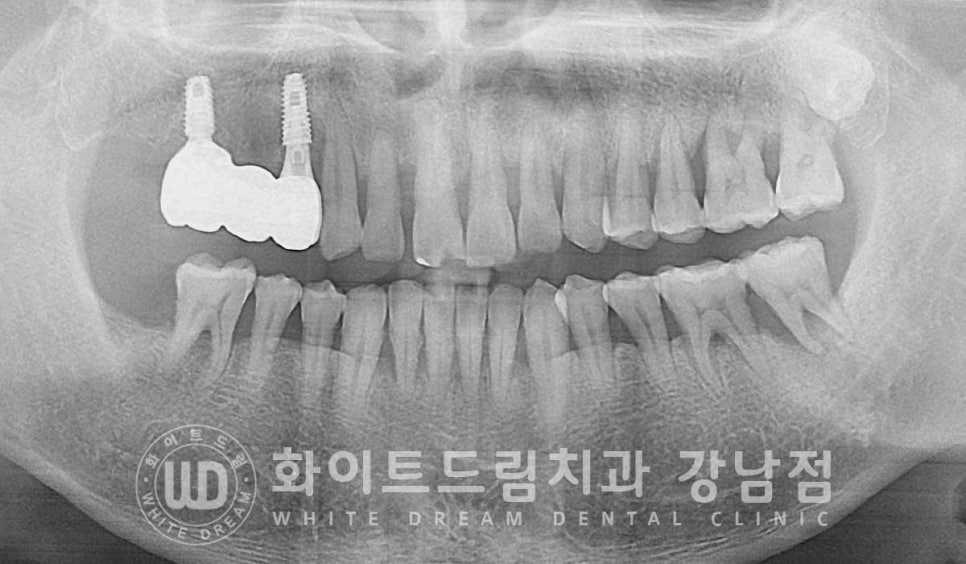

환자분의 수술 4개월 뒤 x-ray 사진입니다.

▲ 수술 당일 / 수술 4개월 후 (24.08.05)

초기 빈 공간이었던 발치와가 모두 새로운 잇몸뼈로 차오른 것이 확인되고

임플란트도 새롭게 형성된 뼈와 단단하게 유착되어 있음이 확인됩니다.

이제 임플란트가 안정적인 고정력을 발휘하니

치아 대신 사용할 수 있도록 치아 모형의 보철을 세팅하면 치료는 마무리된답니다.

저희 강남 화이트드림치과는 임플란트 위에 세팅되는 치아 모양의 보철을

원내 기공실에서 제작하고 있어

보통 외부 기공소로 보내는 치과들에 비해 빠르게 보철 제작 및 세팅이 가능하답니다.

▲ 지르코니아 크라운으로 최종 보철을 세팅하며 치료를 마무리했습니다.

(24.11.01)